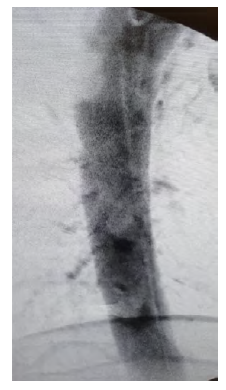

No pós-operatório constatou-se mau posicionamento de material de fixação (Figura 3), pelo que 9 dias depois foi submetido à extração de parafuso protuso em D7 à esquerda sob controlo angiográfico pré e pós-operatório, estando uma endoprótese aórtica torácica na sala para o caso de necessidade de reparação emergente Intra-operatoriamente.

É evidente a presença de material de fixação fazendo protusão sobre a aorta torácica, à esquerda do eixo vertebral.

Não se constatou leak nem alterações da conformação da aorta torácica, não tendo ocorrido qualquer hemorragia pelo trajeto do parafuso (Figuras 4 e 5).